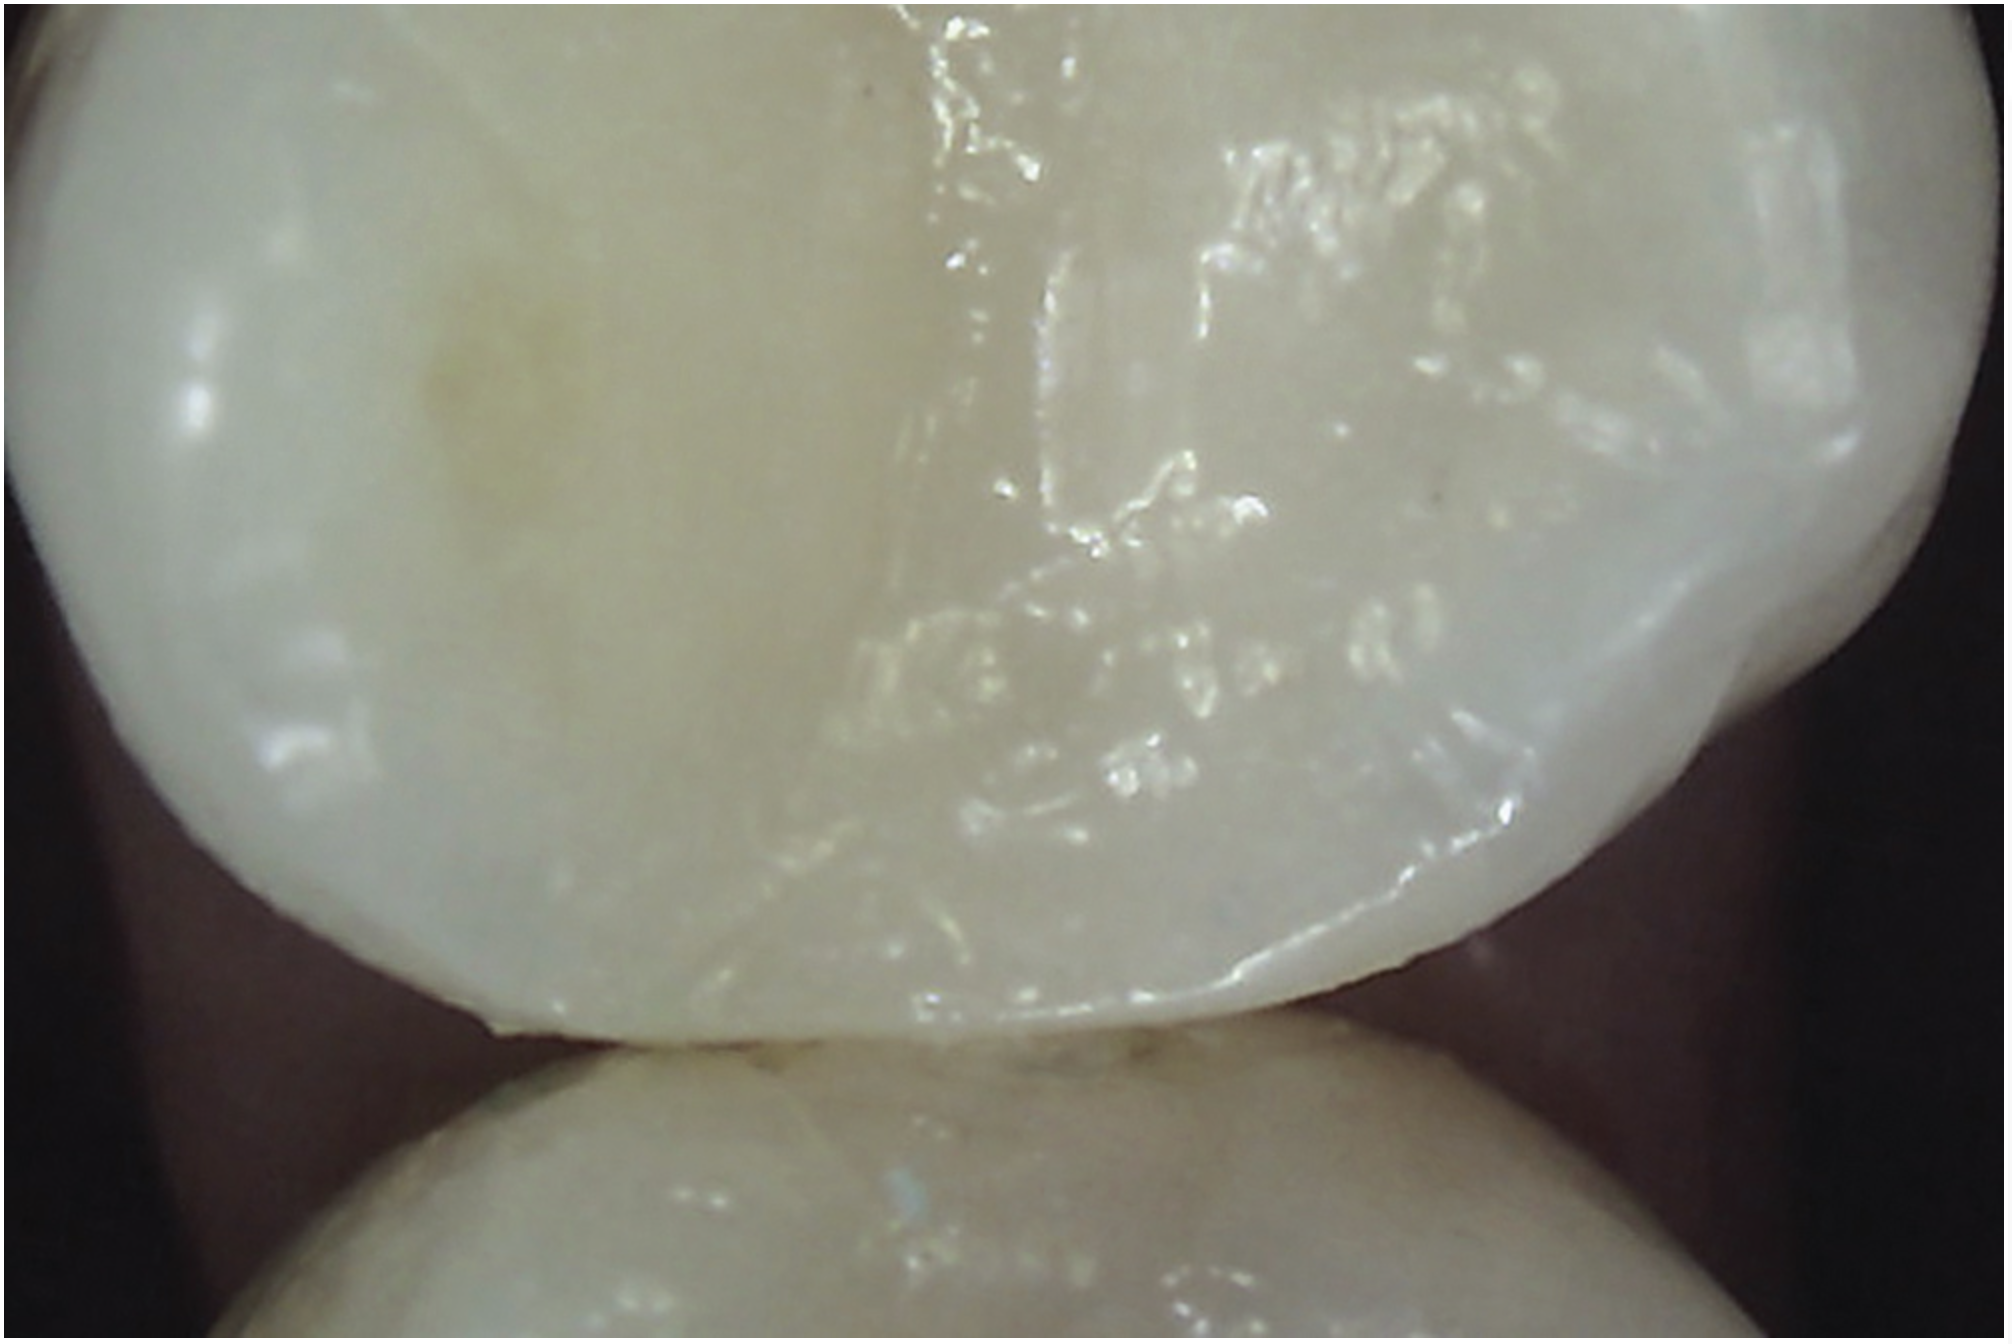

Transillumination

The use of fiber-optic transillumination for crack diagnosis is well documented in the literature.1-3,5,6,8-10,12,15-17,21-23 Teeth with significant cracks transilluminated with a fiber-optic light source will show a well-defined demarcation of blocked illumination at the crack lines, whereas structurally sound teeth will dissipate the light gradually throughout the tooth structure (Figure 3).22 While a variety of transillumination devices have been used to reveal cracks, pen-sized cordless units with a highly collimated light source and that are specifically manufactured for this purpose are ideal for this diagnostic technique. This is mainly because they emit the proper amount of light intensity to highlight cracks, and viewing can be done directly with the eye without using a protective device.22

Fig 3. Transillumination of an asymptomatic maxillary left second premolar blocked by an enamel marginal ridge crack (arrow) (mesio-occlusal view).

Figure 3